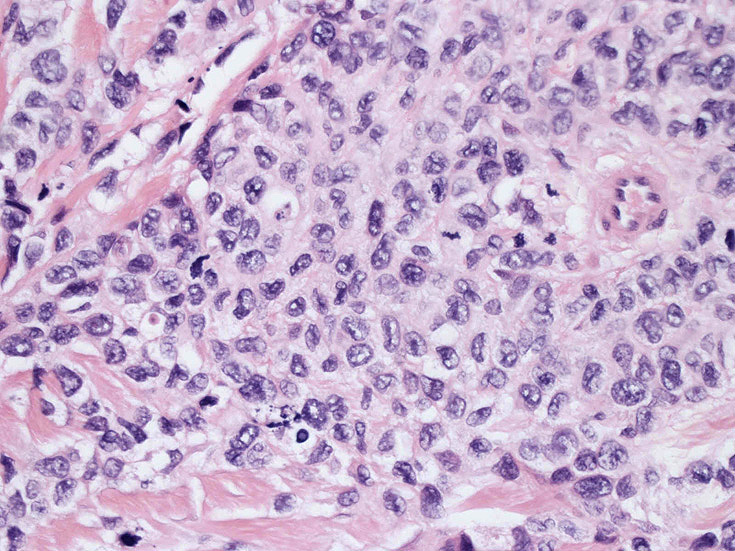

LCSの病理組織所見

Langerhans cell histiocytosisの高悪性度 variantで明らかな悪性像を示すLangerhans cellの腫瘍性増殖と定義される(WHO, 2008)

大型細胞の増殖よりなる腫瘍。縦溝,しわ,切れ込みのある核をもった大型細胞も出現する。クロマチンは顆粒状で核小体も明瞭である。核分裂は >50/10hpfと多い。eosinophilsは少ない。壊死が多発することがある。未分化ないし低分化な細胞像, 組織所見のため鑑別診断は多岐にわたり、的確な免疫染色を行う必要がある。